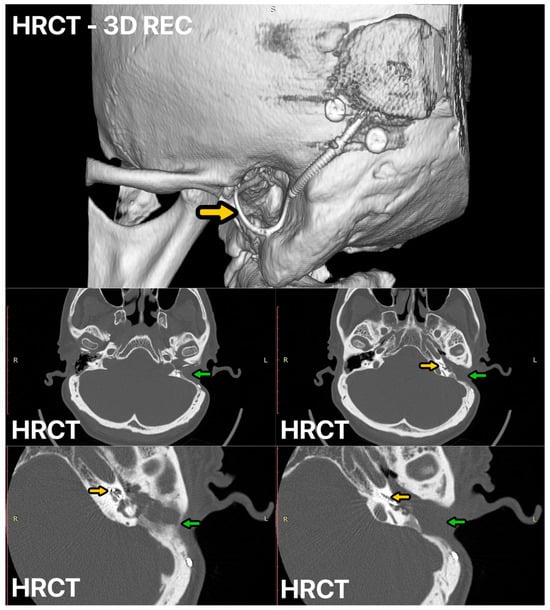

Figure 3.

HRCT of the left ear 12 months after surgery, CI electrode—yellow arrow, mastoid cavity obliterated with temporoparietal fascial flap (TPFF) injected with injectable platelet-rich fibrin (IPRF+)—green arrow.